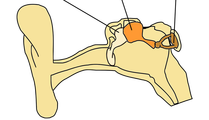

| Partie orange | Incus | 16%

| Partie marron | Stapes | 14%

| Partie beige | Malleus | 7%